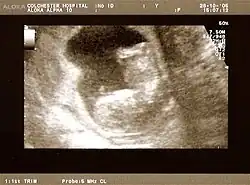

The result of an ultrasonography: a black and white image that shows a clear view of the interior abdomen

Obstetric ultrasonography is routinely used for dating the gestational age of a pregnancy from the size of the fetus, determine the number of fetuses and placentae, evaluate for an ectopic pregnancy and first trimester bleeding, the most accurate dating being in first trimester before the growth of the foetus has been significantly influenced by other factors.[22] Ultrasound is also used for detecting congenital anomalies (or other foetal anomalies) and determining the biophysical profiles (BPP), which are generally easier to detect in the second trimester when the foetal structures are larger and more developed.[23]

X-rays and computerized tomography (CT) are not used, especially in the first trimester, due to the ionizing radiation, which has teratogenic effects on the foetus.[24] No effects of magnetic resonance imaging (MRI) on the foetus have been demonstrated,[25] but this technique is too expensive for routine observation. Instead, obstetric ultrasonography is the imaging method of choice in the first trimester and throughout the pregnancy, because it emits no radiation, is portable, and allows for realtime imaging.[26]

The safety of frequent ultrasound scanning has not been confirmed. Despite this, increasing numbers of women are choosing to have additional scans for no medical purpose, such as gender scans, 3D and 4D scans.[27] A normal gestation would reveal a gestational sac, yolk sac, and fetal pole.[28]

The gestational age can be assessed by evaluating the mean gestational sac diameter (MGD) before week 6, and the crown-rump length after week 6. Multiple gestation is evaluated by the number of placentae and amniotic sacs present.[29]